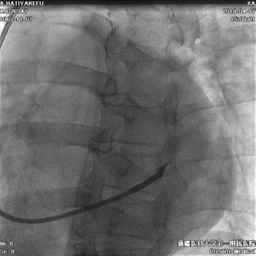

冠状静脉造影

● 通过长鞘造影,先冒烟,确认无夹层,造影后发现侧静脉分支,但不清楚远端情况。

鞘中鞘超选靶血管

● 使用鞘中鞘超选入靶血管

鞘中鞘造影

● 由于入口处有夹角,鞘中鞘无法深入,无论换用90还是130的鞘中鞘,开口处造影都看不到远端血管情况。

尝试导丝送入靶血管远端

● 尝试导丝先行,能否走到靶血管远端。